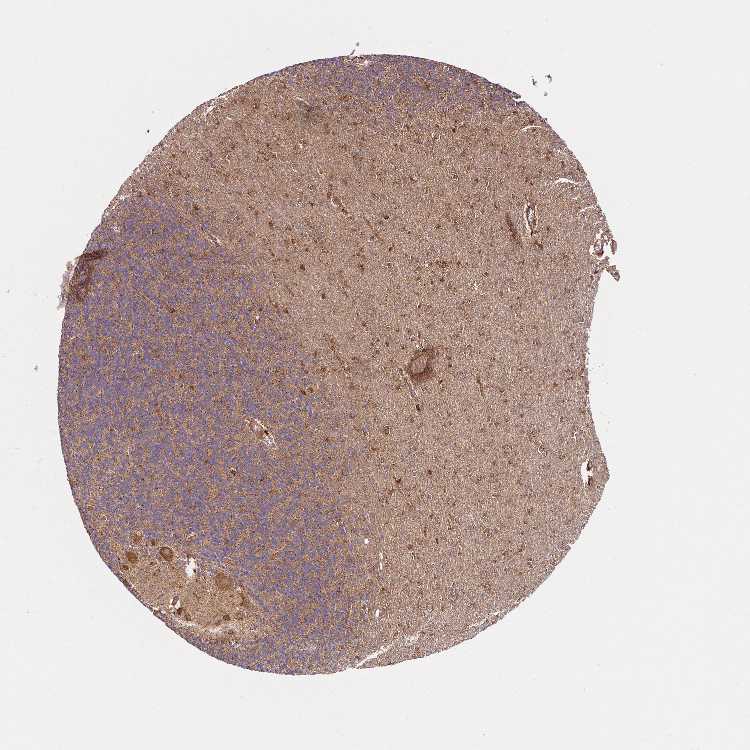

CEREBELLUM - Antibody stainingi

Antibody staining in the annotated cell types in the current human tissue is reported as not detected, low, medium, or high, based on conventional immunohistochemistry profiling in selected tissues. This score is based on the combination of the staining intensity and fraction of stained cells.

Each image is clickable and will lead to virtual microscopy that enables deeper exploration of all samples and also displays staining intensity scores, fraction scores and subcellular localization as well as patient and tissue information for each sample.

Antibody HPA056420Antibody CAB013007

Purkinje cells MediumHigh

Cells in granular layer MediumMedium

Cells in molecular layer MediumMedium